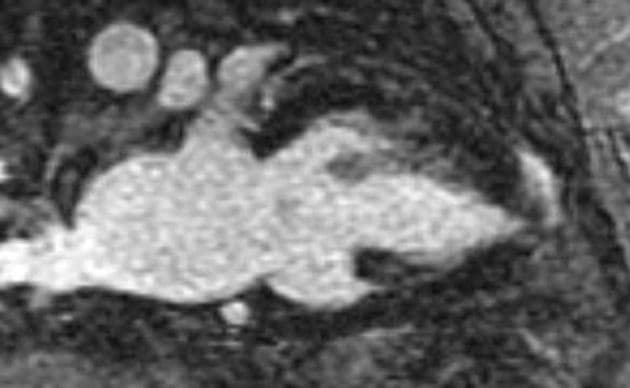

- Cả chuỗi hình ảnh LGE và PSIR có tiêm thuốc đối quang (gadolinium) đều cho thấy xơ hóa thành thất dạng ổ (patchy midwall fibrosis), có liên quan đến lớp dưới nội tâm mạc (subendocardial involvement) tại đỉnh thất (apex).

- Necrosis dưới nội tâm mạc ở đỉnh thất (apical subendocardial necrosis) có thể là nguyên nhân gây đau ngực (chest pain).

- "Tắc nghẽn đoạn giữa thất có thể gây tăng áp lực trong buồng tim và thiếu máu cơ tim vùng đỉnh, dẫn đến hoại tử và xơ hóa lớp dưới nội tâm mạc."

- "Hình ảnh tăng sáng muộn (LGE) ở vùng dưới nội tâm mạc đỉnh giúp phân biệt tình trạng này với các nguyên nhân khác gây dày thành tim vùng đỉnh."

Bệnh cơ tim phì đại dạng đỉnh thất là một thể hình thái riêng biệt của bệnh cơ tim phì đại do bất thường sợi co cơ, chủ yếu ảnh hưởng đến đỉnh thất trái. Khác với thể phì đại vách không đối xứng phổ biến hơn, thể này biểu hiện bằng sự dày lên cô lập ở vùng đỉnh, thường dẫn đến tắc nghẽn đoạn giữa thất và tạo gradient áp lực. Tình trạng căng thẳng huyết động này có thể gây thiếu máu cơ tim vùng đỉnh, hoại tử lớp dưới nội tâm mạc và xơ hóa thành thất dạng ổ, như thấy trên hình ảnh cộng hưởng từ tăng sáng muộn. Sự hiện diện của mô xơ liên quan đến nguy cơ cao hơn về rối loạn nhịp và các biến cố tim bất lợi, làm tiên lượng có thể xấu hơn. Chẩn đoán phân biệt bao gồm nhồi máu cơ tim, bệnh cơ tim do amyloid và sarcoid, nhưng hình ảnh đặc trưng dạng 'bích' trên chụp buồng thất trái và sự vắng mặt của bệnh động mạch vành giúp khẳng định chẩn đoán.